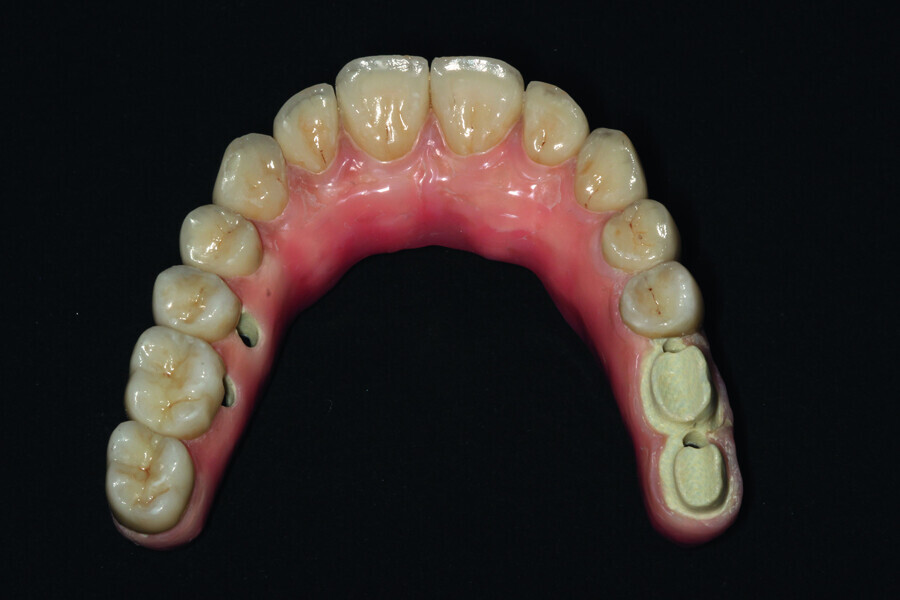

Fig. 14: Porcelain crowns based on a model prior to veneering by means of a pink composite.

Fig. 20: Prosthetic work based on a model where veneering of the gum was started and with crowns.

Fig. 23: Final restoration prior to handover and the placing of crowns.